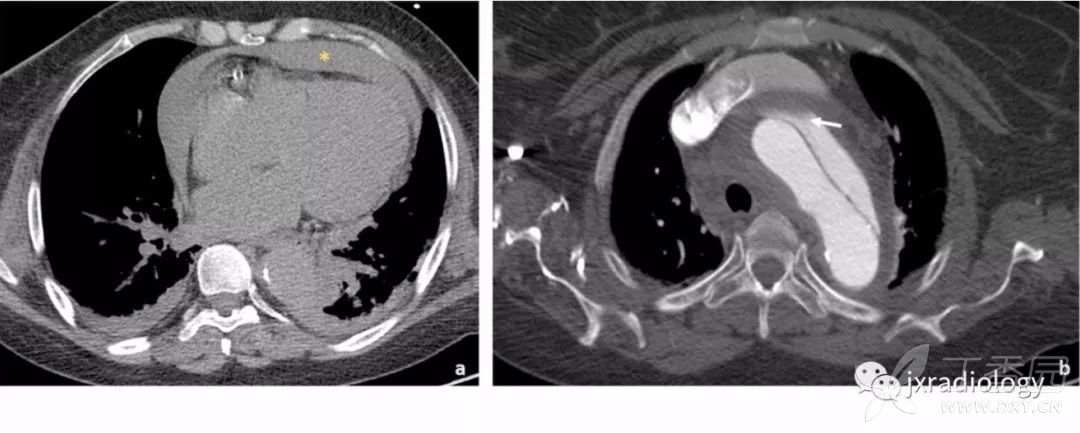

平扫CT发现纵隔,心包或胸膜腔内出现高密度影,可能是胸主动脉破裂的一个征象。增强后主动脉壁不规则或对比剂直接漏出,应提示主动脉破裂。

Stanford A型主动脉夹层患者出现急性心包积液时提示高死亡率,与心包填塞有关( 图16 )。

图16:平扫CT显示自发性高密度心包积液,符合心包积血(a图星号)。双侧胸腔积液可见。增强后示Stanford A型主动脉夹层,并出现假腔的局部血栓形成(b图箭头)。